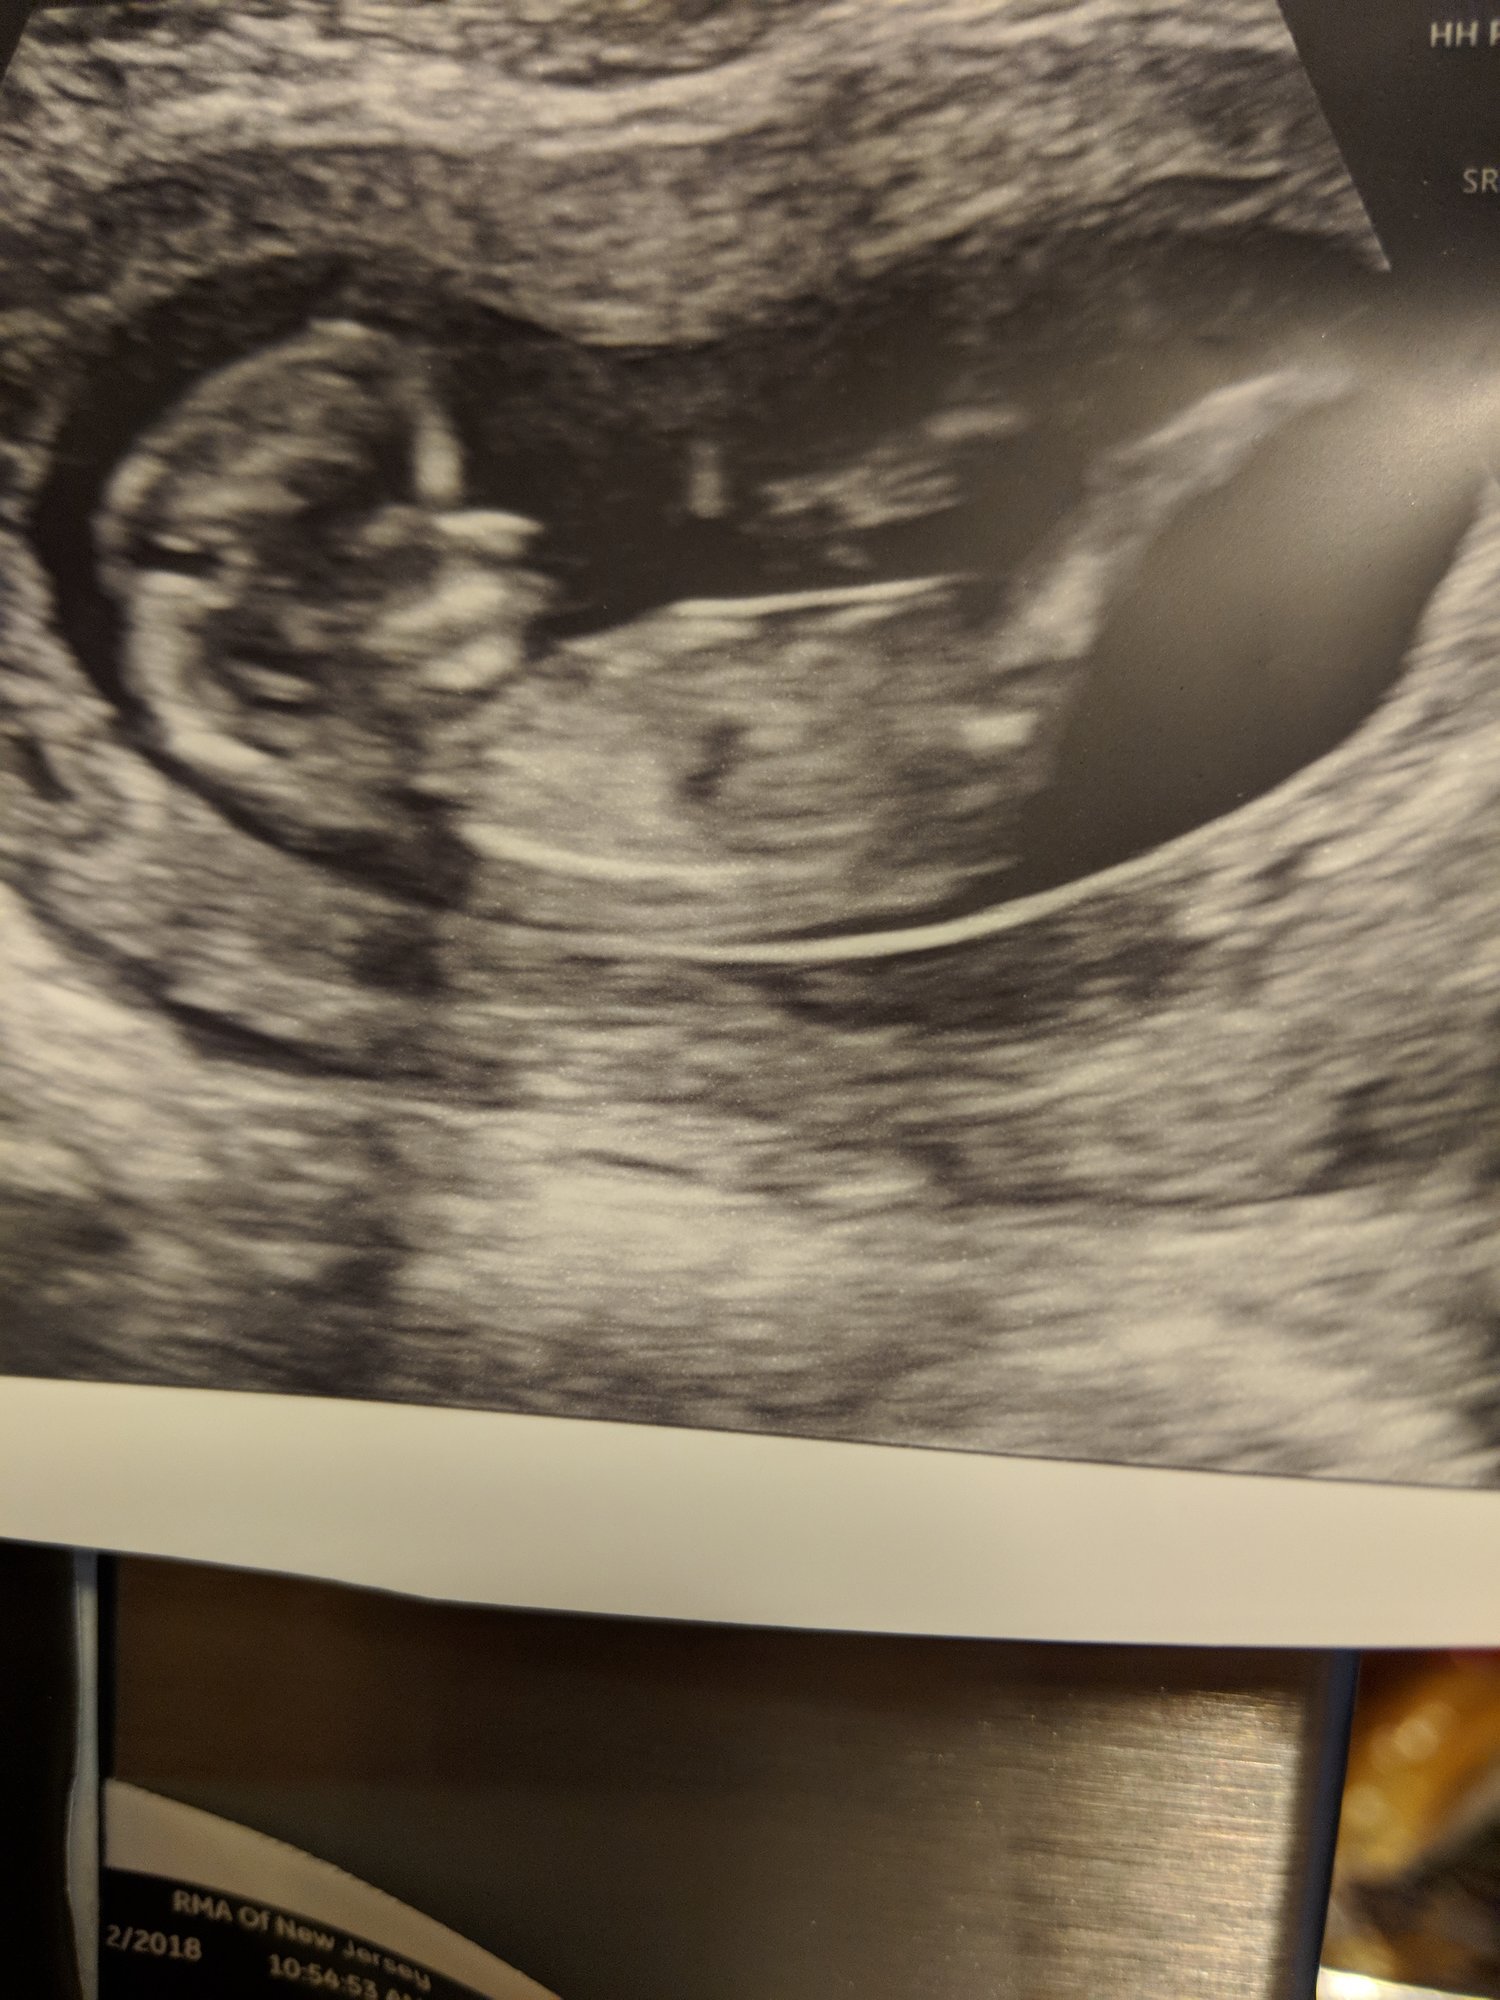

Our little one was 10w 2d at the US, I am now 11w 1d! We have a wiggle worm! He/she was all over the place! HR 170. Love this baby so much already and feeling so blessed! Due 11/27!